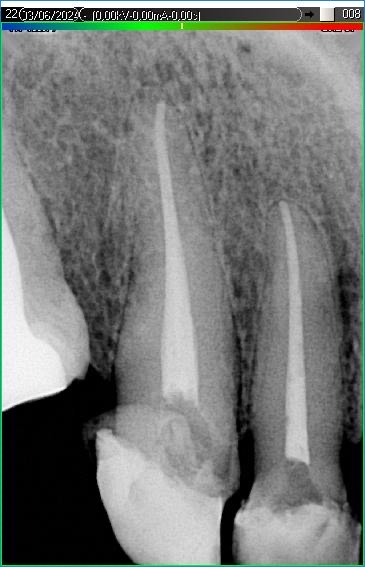

Вилучення інструменту з каналів зуба